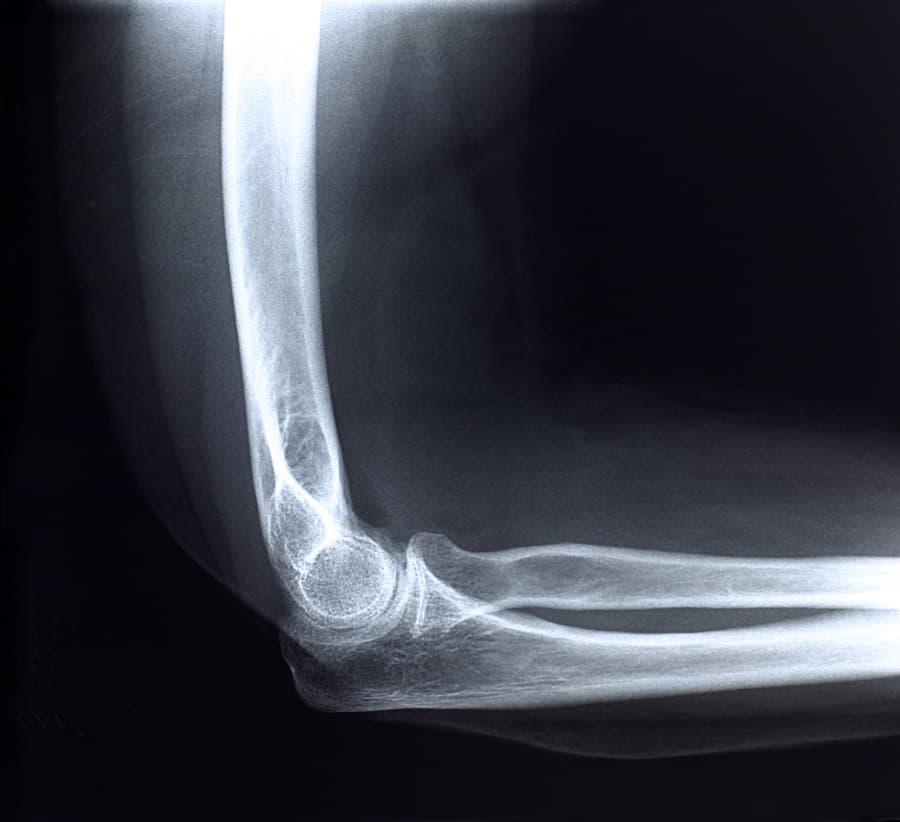

What Is a UCL Injury?

UCL injuries occur when the ulnar collateral ligament (UCL) becomes stretched or torn. UCL injuries are classified in three grades depending on how severely the ligament is damaged:

Rarely, a torn UCL will also pull away a small piece of bone. This is known as an avulsion fracture.